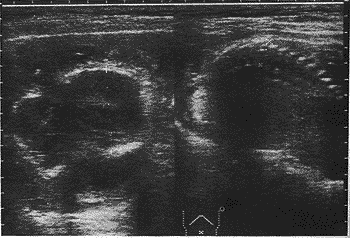

中国超声医学杂志990738 患者女,23岁。孕5个月,时有阴道流血伴腹痛而入院。超声检查:头部光环边缘不清欠规整,可见3个大小不等的低回声反射区,周围有部分强回声线,脊柱明显畸形,腹部界 线不清,在羊水区中可见面积较大的强回声光团反射,边界欠清(图1),其他未见明显改变 。B超诊断:胎儿畸形。行中期引产术,引出畸形胎儿与B超诊断相符合。

图1 头腹联合畸胎儿